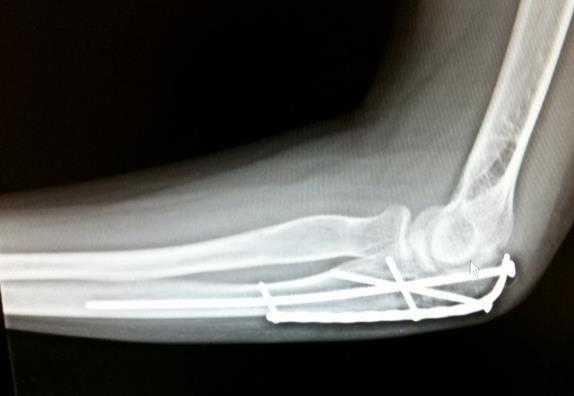

The tip of my elbow broke off when I fell from my bicycle onto my bent elbow. The pain was so extreme I struggled to remain conscious and didn’t realize I’d also fractured two knuckles of my other hand. An ambulance brought me to a local hospital, where admission and surgery was recommended. I called Dr. Joseph Lane, who treats me for osteoporosis, for advise. It was a Saturday evening but he called me right back. He offered admission to NYP Hospital. I will be forever grateful to Dr. Lane for guiding me into the superb hands of orthopedic trauma surgeon Dr. Daniel Dziadosz. Dr. Dziadosz fixed my elbow (literally!) and carefully monitored my progress afterwards. He helped me navigate my return to work and life in general. He was supportive and encouraging throughout my recovery. Dr. Dziadosz operated on my elbow a second time recently to remove the hardware used for the repair a year and a half ago. This surgery was elective and considered together carefully. By Day 1 post-op I knew we’d made the right decision. Two weeks later, now that the stitches were removed and my recovery is progressing quickly, I am actually saddened to have no further reason to see Dr. Dziadosz again. Throughout this ordeal, it’s been easy to develop a warm relationship with him and his team (PA Austin Milan and, in the office, Eloina). Dr. Dziadosz is so smart, funny, engaging and just plain cool, my husband and I both will miss my office visits with him. If I ever have another broken bone, he’s the one I will go to. I’ve had seven other previous orthopedic surgeries to repair broken bones (knee and leg, foot, both shoulders, hand and wrist), from Vail, CO to Long Island, NY. HSS at NYP is the best. From the minute one walks in the door and all the way through to the end result, these affiliated hospitals run like well oiled machines, staffed by well trained and professional staff, with the best surgeons across the country. It makes a huge difference in one’s life. I’m so grateful to Dr. Dziadosz and Austin, Dr. Lane, the anesthesiologists, the hand OT, and nurses, all for their expert and compassionate care. It doesn’t get any better than this. I will be forever grateful!